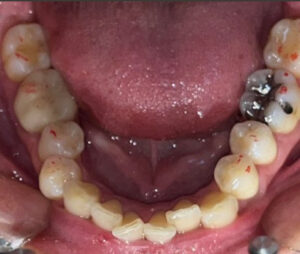

今回は、前歯のレイヤリングジルコニアセラミックの

治療をされた患者さまのご紹介です!

歯周治療、虫歯治療、審美治療の総合的な治療をおこないました。

修復の材料はほぼジルコニアセラミッククラウンで統一しています。

天然の歯は事前にホワイトニングを行い、全体的にトーンアップさせて、

それに合わせてカラーを決めています。

前歯のレイヤリングジルコニアはセラミストのデジタルトライインを行って

作製します!

全体的に綺麗になって患者さまもとても喜んでおられました♪